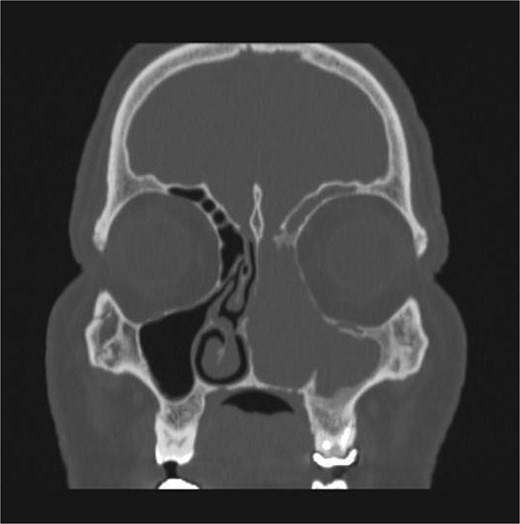

CT showed a heterogeneously enhancing mass completely occluding the left nasal cavity, left ethmoidal, maxillary and frontal sinuses, extending to left pterygopalatine fossa. It is associated with bony erosion of the posterior nasal septum and the left medial maxillary wall (Figs 1 and 2). Findings were suggestive of inverted papilloma vs sinonasal malignancy. Therefore, biopsy was recommended.

Coronal section of CT paranasal sinus with contrast soft tissue window showing the mass occupying the left nasal cavity and extending to maxillary and ethmoidal sinus.